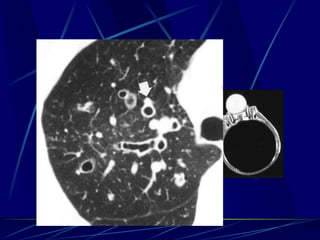

Finger in Glove Sign

Visible on chest radiographs or CT

•Indicates mucoid impaction within an obstructed bronchus

•Characterized by branching tubular or fingerlike opacities

ABPA: glove-fingershadow dueto mucoid impaction in central

bronchiectasisin a patientwith asthma.